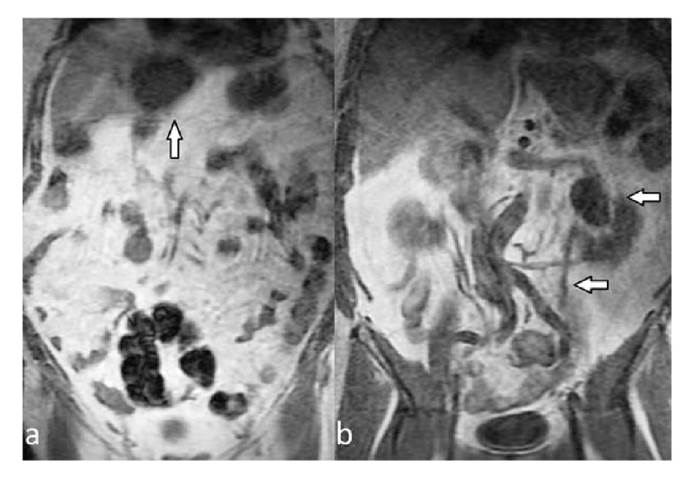

Figure 1 Coronal T1-weighted images show hypointense cysts (arrows) located in both kidneys (a). On the coronal-T 1 weighted sequence (b), a unilateral sacral hypointensity at the level of sacroiliac joints was detected (arrow); this finding is consistent with unilateral sacroiliitis and it was not detectable on conventional MR sequences.

Figure 2 A hypointense mass (arrow) is observed in the liver (a). Coronal T1-weighted images show pelvic dilatation of the left kidney (arrows). There is also dilatation of the left ureter (b).